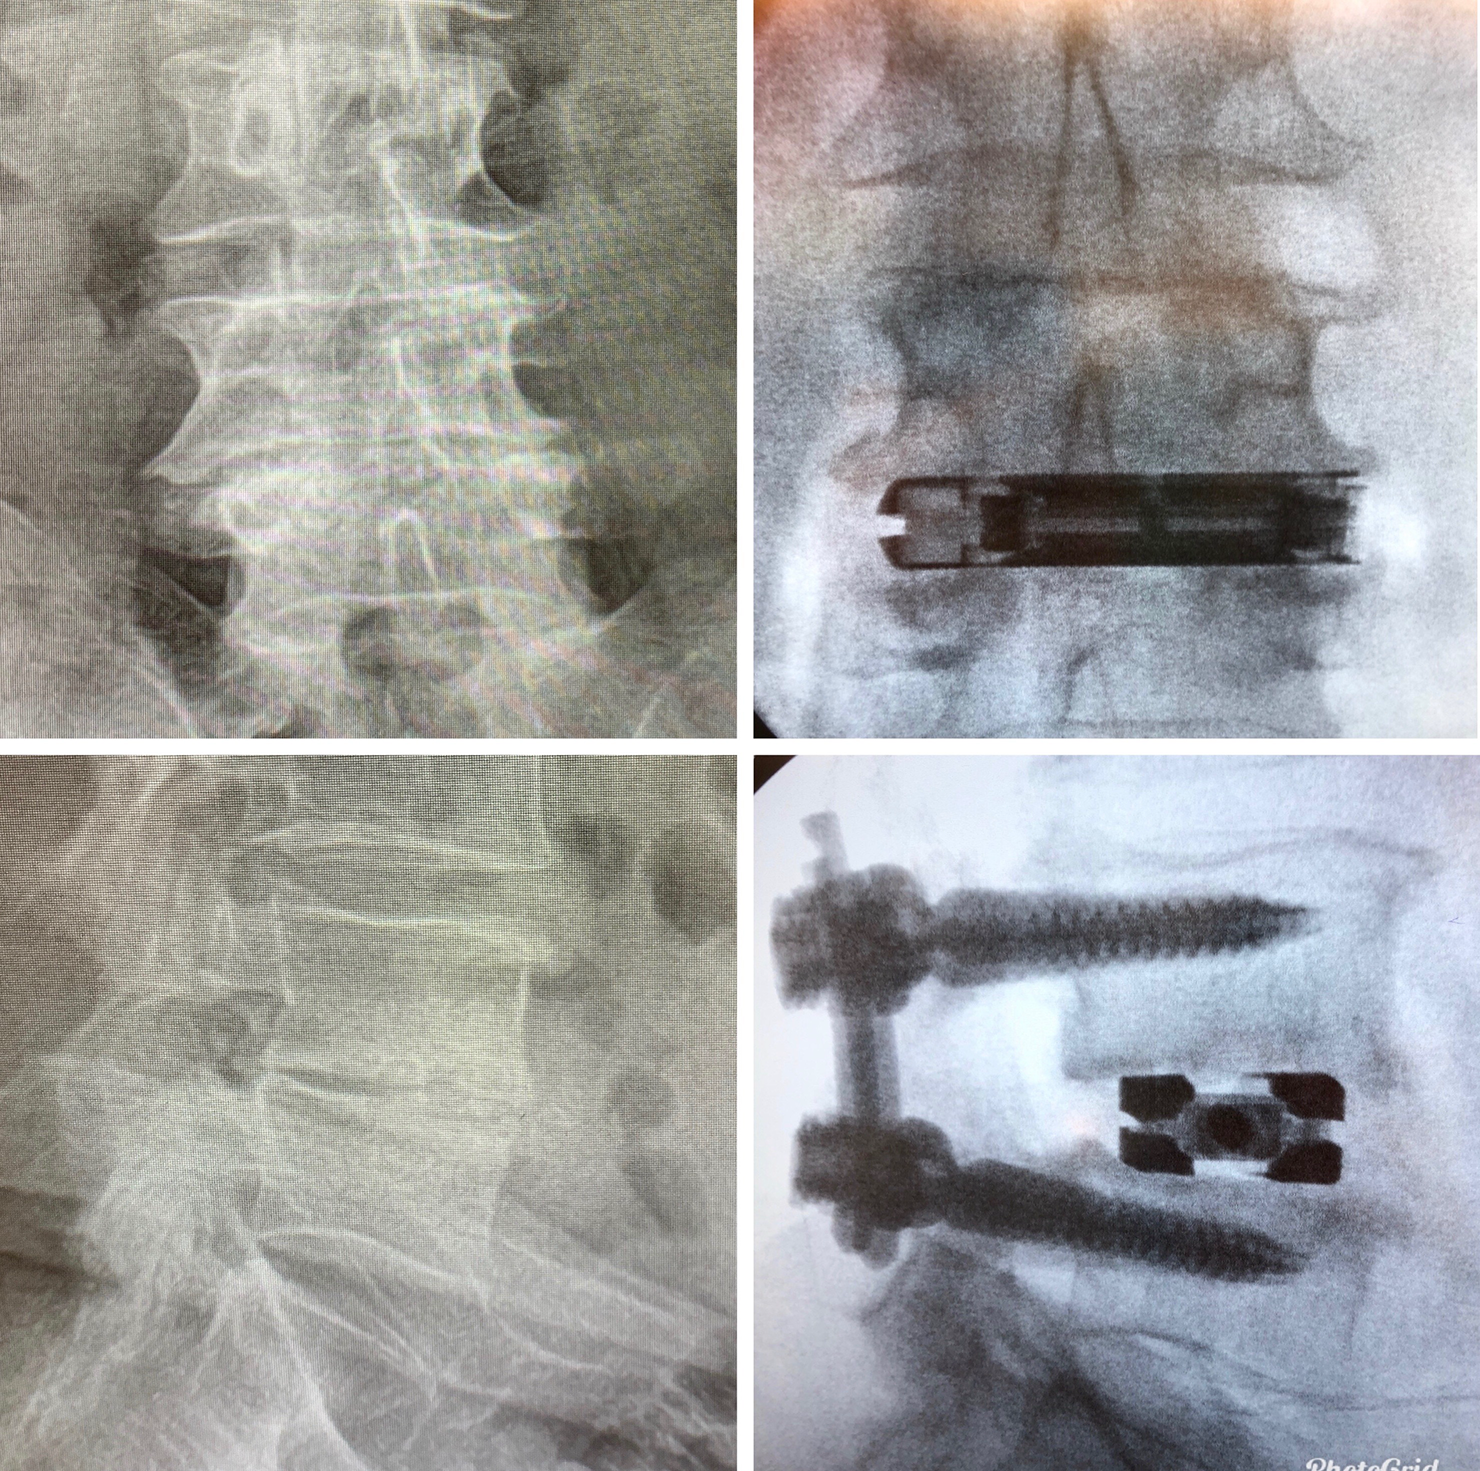

The dualX® LLIF solution is a comprehensive expandable interbody cage system for small portal access. dualX® LLIF is designed to minimize neural retraction while achieving maximum implant geometry.

The procedure is performed completely through an 18mm opening, reducing the potential psoas retraction up to 50%.

Large, center bone graft chamber for post-expansion grafting

Vertical expansion assists in direct and indirect decompression

Heights 7mm* expanding to 17mm*

Width 13mm expanding to 22mm

Final Length 40 to 60mm

0°, 7°, 12° and 18° Lordosis*